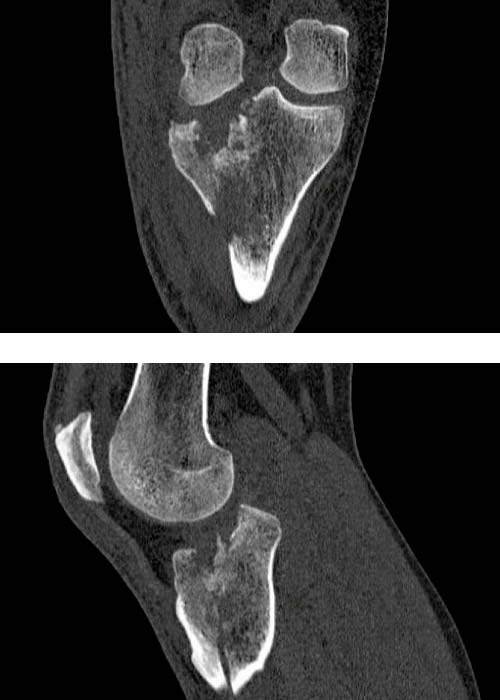

Se realiza estudio con pruebas complementarias (radiografías y TAC):

Radiografía anteropostesior y lateral de rodilla derecha en la que se observa una fractura de meseta tibial con apertura y separación longitudinal anterolateral con trazos fracturarios diafisarios.

En TAC se objetiva una fractura conminuta de la meseta tibial con hundimiento del platillo tibial anterolateral con líneas de fractura diafisarias anteriores, mediales y posteriores.

Diagnosticado de fractura meseta tibial según la clasificación de Schatzker, tipo II (combinación de hundimiento y separación) y tipo VI con disociación de la metáfisis y la diáfisis.